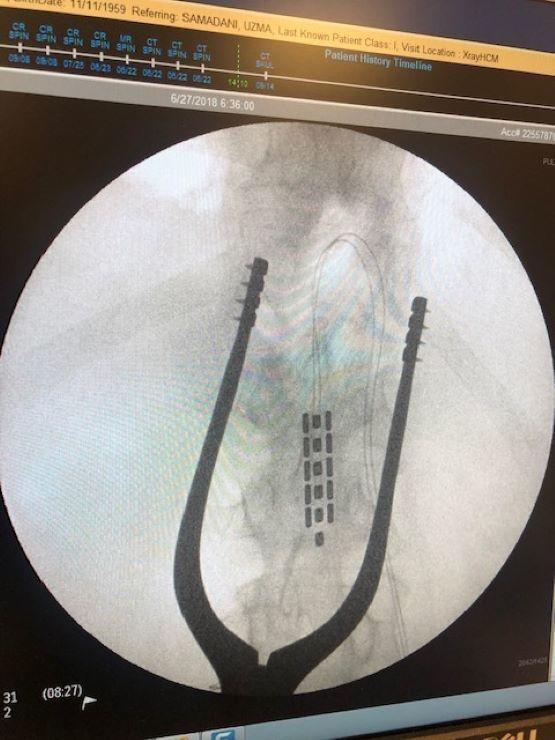

Epidural Spinal Cord Stimulation

What it is

Epidural stimulation describes a process where electrical current is applied to the spinal cord. Stimulation is applied through a small implant that is placed over the dura (protective layer around the spinal cord). For people with spinal cord injury, stimulation is applied below the level of injury. The intervention is typically a 45-minute outpatient procedure (statement by Neurosurgeon Dr. Darrow, U Minnesota). To date, stimulation has resulted in a wide array of benefits. For example, we recently published work showing that stimulation allowed volitional motor function below the level of injury for people with clinically-complete injuries of more than 5-10 years. This was achieved without rehabilitation and occurred the first time we turned stimulation on. Of course, rehabilitation is likely crucial to maximize the benefits of the stimulation. We have also observed reductions in bowel time, improved sexual function, improved lower-urinary tract function, more stable blood pressure, and increased exercise capacity.

How it works

In almost all clinically-complete injuries there are some preserved connections across the site of injury, but these connections are not functional in a normal state (i.e., dormant). By applying electrical current to the nervous system circuits within the spinal cord below the level of injury, we are able to re-awaken these dormant connections. This functional re-connection allows for the brain to recover some of the lost control over systems below the level of injury. Furthermore, the spinal cord is not simply a relay pathway (i.e., highway) transmitting information from the brain to the periphery. It also contains intricate interconnections that can process information and coordinate outputs with little input from the brain. Stimulation also helps to re-awaken these complex interconnections. Together, the awakening of dormant pathways and activation of complex interconnections with stimulation often leads to meaningful improvements in function for people with spinal cord injury. We are harnessing these concepts to provide health solutions for people with spinal cord injury.